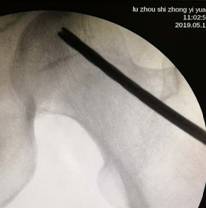

經(jīng)過術(shù)前與麻師團(tuán)隊(duì)詳盡的討論及預(yù)案制定后,手術(shù)醫(yī)師首先為吳先生實(shí)施雙側(cè)股骨頭壞死髓芯減壓,即打開一個(gè)像筷子大小的“隧道”孔后,再通過“隧道”將分離的血小板注射進(jìn)吳先生骨頭壞死區(qū)域。整個(gè)手術(shù)僅抽取了80毫升血液,耗時(shí)數(shù)十分鐘,術(shù)后三天患者出院。

術(shù)中,為患者打通“隧道”,注入血小板